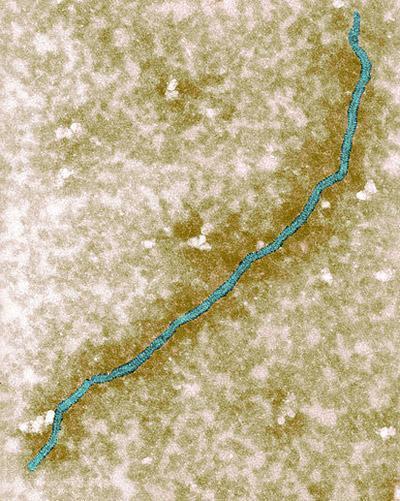

İlk defa Malezya'nın Nipah bölgesinde bir salgınla başlayan virüsün ayrıca biyolojik silah olduğuna dair iddialar da bulunuyor.

En çok Singapur, Malezya, Hindistan ve Bangladeş'te görülen virüs, meyve yarasaları aracılığıyla taşınıyor.